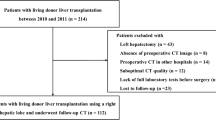

In this study, we analyzed 40 RGB images, which refer to 40 different potential liver donors. HS was assessed with histopatological analysis performed after liver biopsy.

Biopsy was performed during procurement, taking surgical triangular hepatic samples up to 2 cm. One pathologist analyzed the histological sections. Steatosis was visually assessed based on the percentage of hepatocytes with intracellular large lipid droplets by using a semicontinuous scale [0:5:100%].

From the dataset, 20 livers referred to discarded grafts, as with a HS \(\ge 60\%\). The remaining 20 livers had a HS \(\le 20\%\) and were transplanted. Images were acquired with a smartphone RGB camera. Image size was \(1920\times 1072\) pixels. All the images were acquired with open-surgery view, as no laparascopic procurement is performed for cadaveric donors [14]. Challenges associated with the dataset included:

Visual samples of liver images are shown in Fig. 3.

From each image, liver manual segmentation was performed to separate the hepatic tissue from the background (Fig. 4). The manual segmentation of the liver images was performed with the help of the software MATLAB ®. The liver contour in each image was manually drawn by marking seed points along the lived edges, which were then connected with straight lines by the software.

The whole image was then divided in non-overlapping patches of size \(100\times 100\) pixels starting from the top-left image corner. We chose such patch size as image-patch size is usually of the order of magnitude of \(10^2 \times 10^2\) pixels (e.g., [32]). The most right part of the image, for which it was not possible to select full patches, was discarded. This did not represent a problem since the liver was always displayed at the center of the image. A patch was considered valid for our analysis if it overlapped with at least 90% of the liver mask.

To have the same number of patches from each patient, we first computed the minimum number of image patches that we could obtain among all images, which was 15. Then, we randomly extracted 15 patches from all the other images. As result, our patch dataset was composed of 300 patches extracted from transplanted liver and 300 from non-transplanted ones. Sample patches for transplanted and non-transplanted livers are shown in Fig. 5.